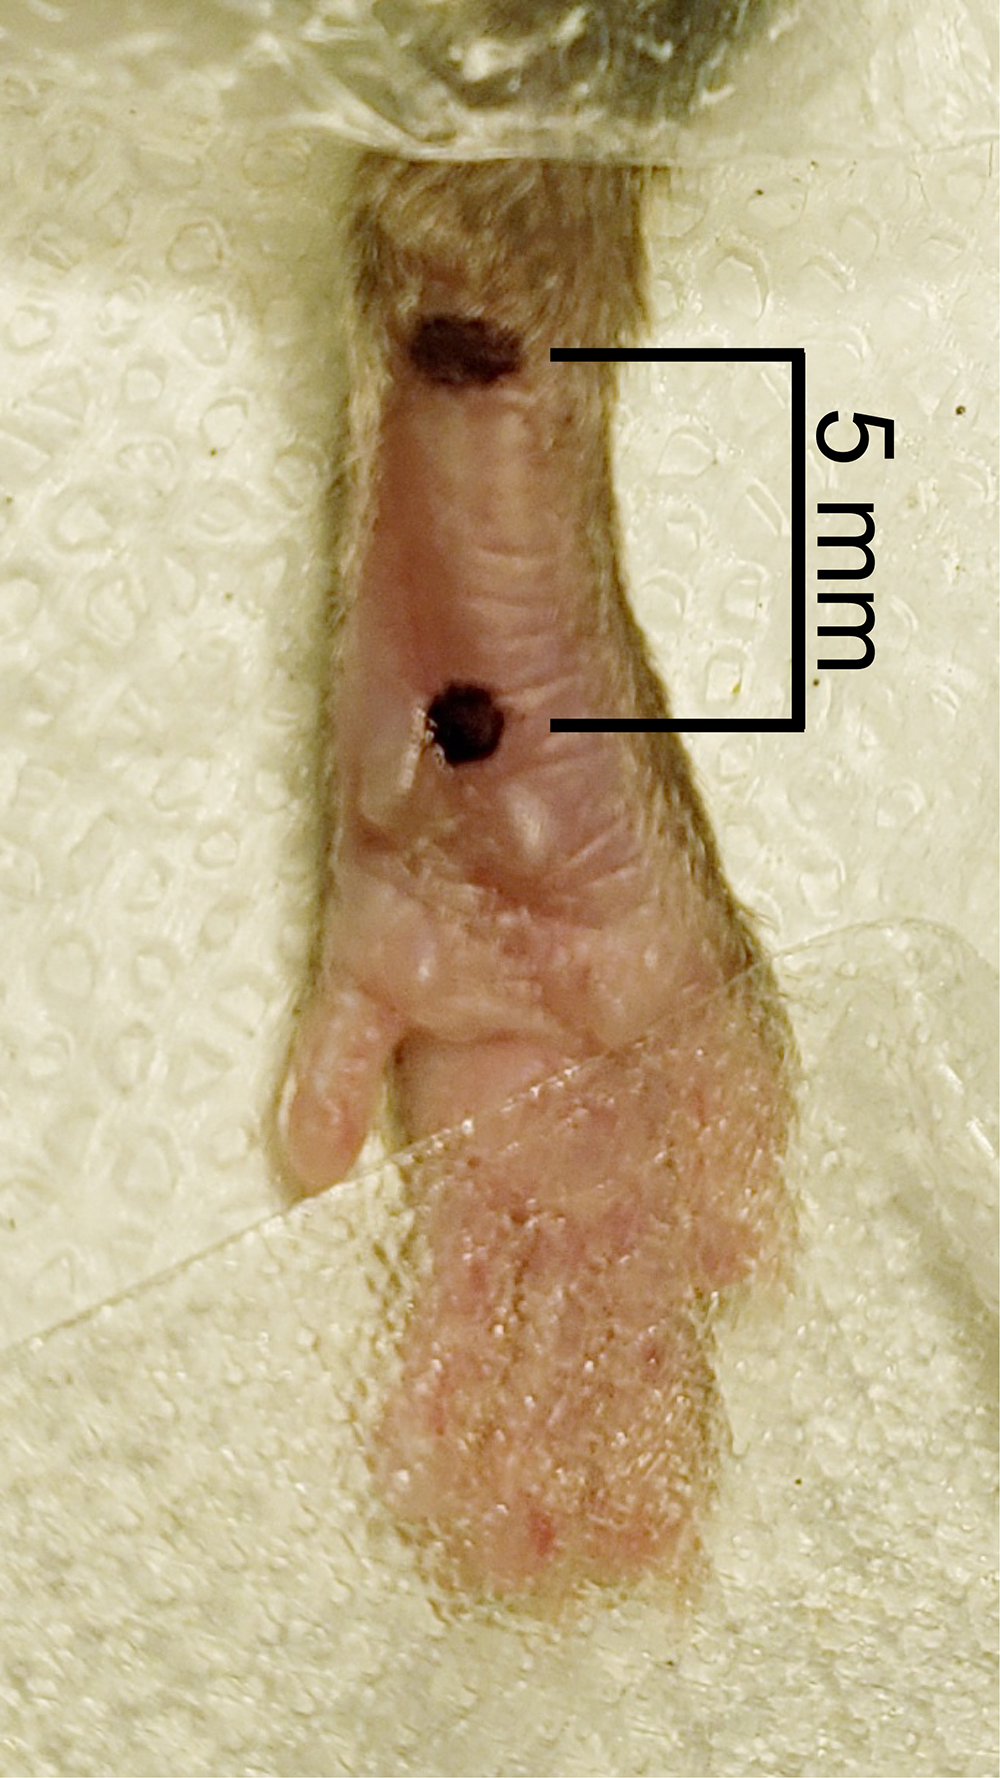

- Measure 2 mm from the proximal edge of heel using a digital caliper and place a dot with a permanent marker at this location in the middle of the hindpaw. From the first dot, measure 5 mm towards the toes down the center of the hindpaw and place a second dot (Figure 4).

Figure 4. Measurement of incision. Two dots were placed in the middle of the hindpaw, one 2 mm from the heel and the second 5 mm from the first dot. - Check that the mouse is fully anesthetized by lightly pinching the most medial toe (most likely this toe could not be secured by the surgical tape) with the forceps. If the mouse flinches, wait until the mouse no longer reacts to the toe pinch before proceeding to Step 9.

- Stabilize the hindpaw by placing the forceps on each side of the heel and make a longitudinal incision through the skin and fascia from the first dot to the second dot (Figure 5).

Figure 5. Cutaneous incision. A 5 mm longitudinal incision was made with a No. 11 scalpel. - Spread the skin away from the flexor digitorum brevis muscle with the forceps. Elevate the flexor digitorum brevis muscle by inserting one end of the curved forceps underneath the lateral edge of the flexor digitorum brevis muscle and pushing the forceps through to the medial side of the muscle (Figure 6).